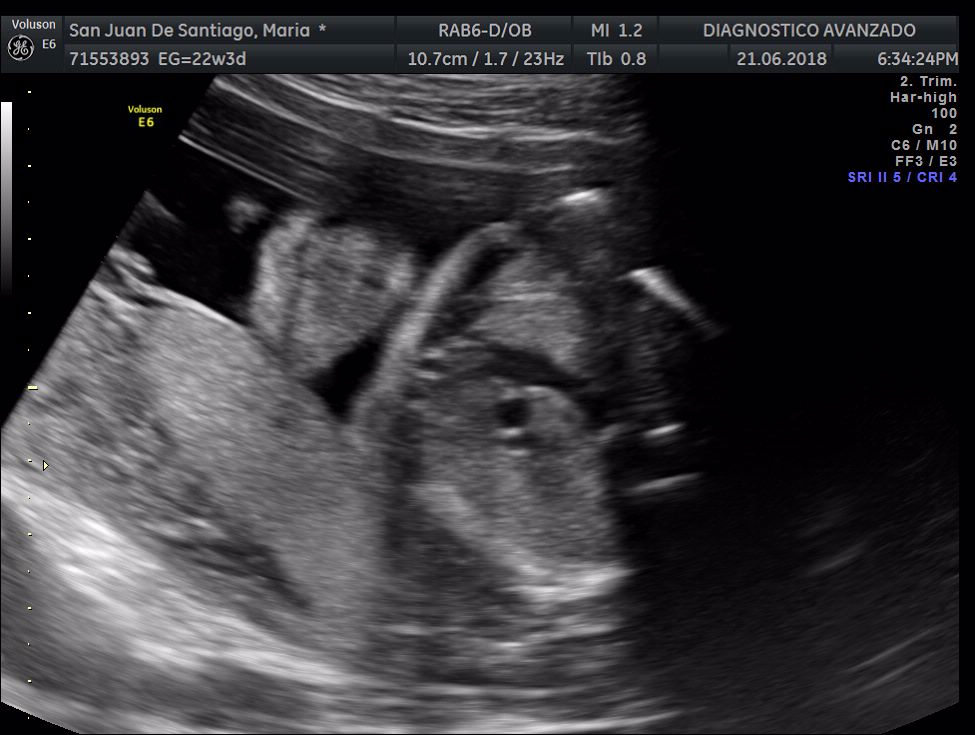

¡Hola a todos! Hoy hemos ido a hacer la tradicional ecografía 3D de la niña, os dejamos todo el material (aunque es un poco demasiado).